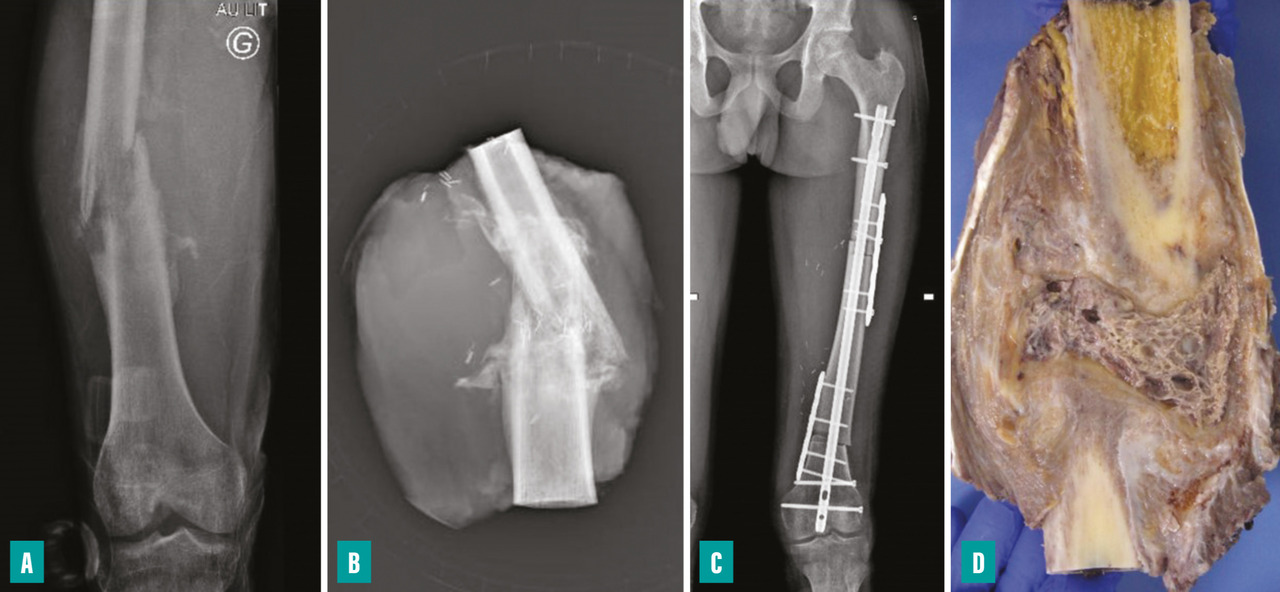

La survenue d’une fracture pathologique rend plus difficile l’obtention de marges saines du fait de la dissémination de l’hématome dans les tissus mous. Elle ne semble pas augmenter le risque de récidive locale – à la condition d’obtenir des marges saines – et ne constitue donc pas une indication d’amputation (fig. 3). Lorsqu’elle survient en cours de traitement, elle fait craindre une mauvaise réponse à la chimiothérapie, qui pourrait expliquer le moins bon pronostic de ces patients.3,4